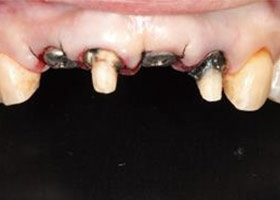

治療前,X光片及口內照片。

舊牙冠拆除後,

右上側門牙及左上正中門牙斷裂。